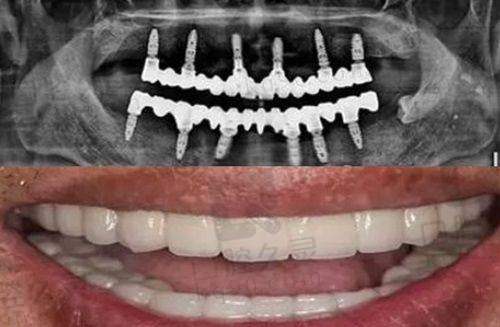

说到广州鼎植口腔,不得不提的就是他们在种植牙领域的出色表现。医院引入了多项精良的种植技术,受到许多患者的青睐。

VIIV种植技术

广州鼎植口腔尤其以其独特的VIIV种植技术驰名。这项技术是由鼎植医生团队与院士们合作研发的,能够有效解决牙槽骨缺失等复杂情况。通过这种技术,医生可以实现“穿颧种植”和“穿翼板种植”,大大提高种植的效率和成功几率,减少患者的痛苦。